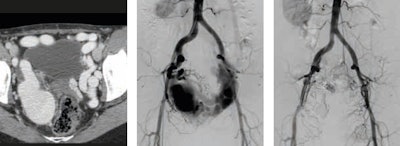

Rare findings, such as arteriovenous malformations, are extremely challenging and require accurate diagnosis and appropriate treatment, especially if they are high-flow and/or extensive lesions. Embolization with coils and 98% ethanol is just one of the many existing treatment possibilities (see figure 3).

Figure 3: Yakes type IIIa arteriovenous malformation: multiple arteriovenous fistulas into the wall of a single outflow aneurysmal vein -- before and one year after embolization. Image courtesy of Dr. Krzysztof Pyra."The radiology curriculum should put much more emphasis on expanding clinical knowledge, so that radiologists become even better partners in the decision-making process on the patient's pathway. The diagnostician may -- or even should -- advise on implementing minimally invasive therapeutic methods in particular cases," Pyra said.